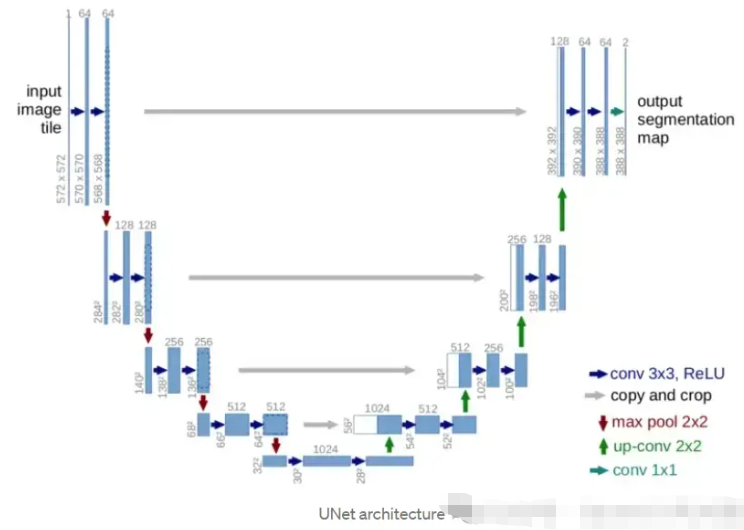

【1】您能解释一下什么是UNet架构以及它是如何使用的吗?

UNet架构是专门为图像分割任务设计的深度学习模型。Olaf Ronneberger 等人在论文“U-Net:用于生物医学图像分割的卷积网络”中介绍了它。

UNet架构由两部分组成:收缩路径和扩展路径。收缩路径是一系列卷积层和最大池化层,用于对输入图像进行下采样并提取特征。扩展路径是一系列卷积层和上采样层,它们对收缩路径中的特征图进行上采样,并将它们与输入图像中的特征组合以生成最终的分割图。

UNet 架构通常在大型带注释图像数据集上进行端到端训练,以预测每个图像的像素级分割图。可以训练模型来分割单个类别或多个类别,具体取决于具体任务。

UNet 广泛应用于各种图像分割任务,例如医学图像分割、卫星图像分析和自动驾驶车辆中的目标检测。它以其处理高分辨率图像和生成准确分割图的能力而闻名。

【2】UNet架构的主要组成部分是什么,它们如何协同工作?

UNet架构的主要组成部分是收缩路径、扩展路径和跳跃连接。

收缩路径是一系列卷积层和最大池化层,它们对输入图像进行下采样并从中提取特征。卷积层将一组滤波器应用于输入图像并生成特征图,而最大池化层通过在像素窗口内获取最大值来对特征图进行下采样。

最终的分割图是通过对收缩路径中的特征图进行上采样并将其与扩展路径中输入图像的特征相结合而创建的,扩展路径是一系列卷积层和上采样层。卷积层将一系列滤波器应用于上采样的特征图以创建最终的分割图。相反,上采样层通过重复像素窗口内的值来提高特征图的空间分辨率。

这些连接(称为“跳跃连接”)绕过扩展路径中的一个或多个级别,并将它们链接到收缩路径中的相应层。它们使输入图像中的高级和低级信息能够合并到模型中,从而提高分割图的精度。